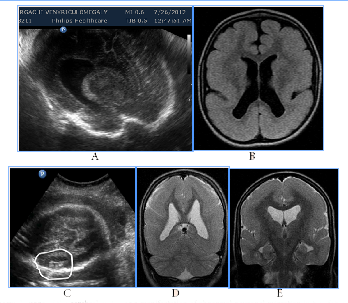

To distress associated antenatal US features of fetal brain could include signs of cortical dysplasia, antenatal intraventricular hemorrhage and PVL (Figure 9) (Figure 10). PVL in the form of small cyst was observed in two fetuses with different premorbid background one fetus with severe prenatal distress and the others with neuroinfection. Particularly attention deserved severe postnatal aftermath of fuzziness and reduced contrast of the fetal brain structures due to cerebral edema and cortical laminar necrosis at 5cases which had different pathogenetic background (Figure 10). Such contrast of structures looked like a result of wrong exposure while getting a picture, but thats were real images, with progression of edema structures looked absolutely "blurred" and cystic PVL lesions were detected. Postnatal catamnesis of all cases was extremely unfavorable.

Figure 10Fetal distress associated small-cystic PVL in the fetus and newborn.

Among of infection-associated echographic signs of the fetal brain anomalies (for CMV, maternal VIH/AIDS, also unclassified etiology of neuroinfection) there were revealed changes, mainly of the intraventricular, subependymal and periventricular localization (Figure 11) (Figure 12) subependymal cysts, heterogeneous periventricular echogenicity, intraventricular adhesions, antenatal intraventricular haemorrage, hydrocephalus, cerebral edema signs, cystic PVL and signs of disgenetic processes - partial agenesis of the corpus callosum and cortical dysplasia.

Figure 11Infection-associated fetal brain abnormalities (neuroinfection of unknown etiology), two cases.

Figure 12Infection-associated fetal brain abnormalities (maternal VIH/AIDS), fetal NSG and postnatal MRI scans.

Figure 10 Fetal distress associated small-cystic PVL in the fetus and newborn. A) 31 GW, severe IGR, fetal metabolic acidosis, fuzziness and reduced contrast of the brain structures due to cerebral edema, skull deformation due to cortical necrosis, small cysts PVL in the intermediate zone (arrow). B) NSG of the newborn's brain of on the 2nd day of life, progressive small-cystic PVL. Neonatal death.

Figure 11 Infection-associated fetal brain abnormalities (neuroinfection of unknown etiology), two cases: A) Hydrocephalus, partial agenesis of the corpus callosum and subependymal cyst, infant death in 5 months. B) Intraventricular adhesion, adverse CPO.

Figure 12 Infection-associated fetal brain abnormalities (maternal VIH/AIDS), fetal NSG and postnatal MRI scans. A) Significant fetal hydrocephalus with a total extension of the ventricular system, cystic PVL (arrow). B) MRI after birth, cystic lesions on both sides of the shell, progressive internal and external hydrocephalia. Neonatal death.